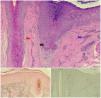

El dermatoscopio reveló eritema y descamación perifolicular moderados, con algunos cabellos aislados. Se realizaron 2biopsias cutáneas. El estudio histopatológico reveló daños en la capa basal de los folículos pilosos, con presencia de abundantes queratinocitos necróticos, asociados con fibrosis lamelar, fibrosis en el corion cutáneo adyacente e infiltrado inflamatorio mononuclear moderado localizado en el infundíbulo folicular. Las tinciones Fontana Masson, S100 y MelanA resultaron negativas para melanocitos (fig. 3), lo cual confirmó el diagnóstico de coexistencia de AFF y vitíligo en la misma lesión. Se calculó un valor de 1,1031 en la escala Vitiligo Extent Score (VES) y de 11,6 en la escala Frontal Fibrosing Alopecia Severity Score (FFASS).

A) Histopatología: vacuolización de la capa basal, abundantes queratinocitos necróticos (flecha negra), fibrosis lamelar dérmica (flecha roja) e infiltrado inflamatorio mononuclear moderado (flecha azul). B) Tinción de Fontana Masson negativa para la presencia de melanocitos. C) Tinción inmunohistoquímica MelanA negativa para la presencia de melanocitos.